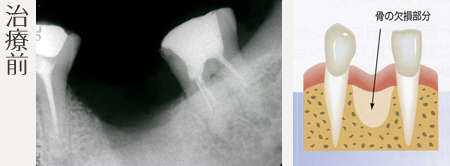

【インプラントの治療事例】

インプラント治療の前に(骨の環境整備)骨造成(GBR)

骨造成(GBR)

インプラント治療に必要な骨の幅、高さが足りない場合、インプラント埋入の前に骨補填材による骨造成をします。

骨のない部分に膜(GTR膜)を貼り、自家骨、骨補填剤を使用して欠損部分の骨を再生します。

インプラントするには骨の高さが足りない。